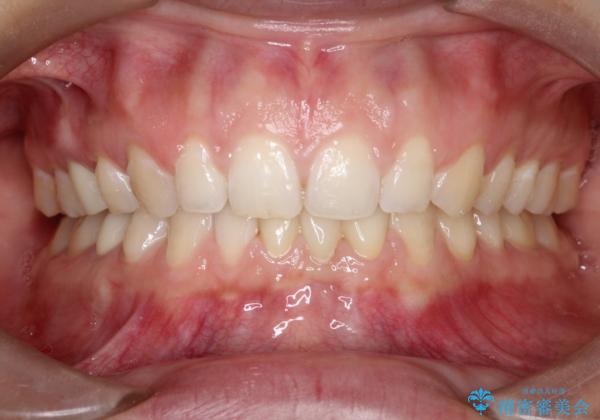

- 歯と歯の間に隙間があることを主訴に来院されました。

短期間での治療終了を希望され、ワイヤー矯正にて治療を行い1年ほどで治療を終了しております。

下顎前歯は矯正後補綴治療を行なっております。

期間や仕上がりで大変満足していただきました。